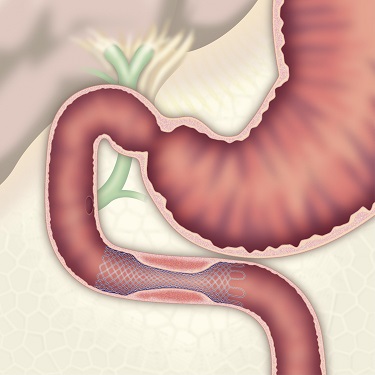

胃・大腸などの内視鏡検査とは異なり、膵臓・胆道では内視鏡的逆行性膵管胆管観察法(通称ERCP)というX線検査などを組み合わせた方法が行われます。十二指腸までスコープを進め、その先は内視鏡の先端から造影カテーテルという細いチューブを胆管や膵管に挿入して、造影剤を直接注入し、レントゲン写真を撮影することで、胆嚢や胆管及び膵管の異常を詳しく調べる検査です。同時に胆道膵癌の病変細胞診断や胆道閉塞のステント治療、胆管結石・膵石の治療にも応用されています。また、当院では、胃・胆道・膵臓切除手術後で、通常ERCPスコープでは乳頭に到達できない症例に対しては、小腸バルーン内視鏡を使ってERCPを行っております。

胃切除後バルーン内視鏡ERCP